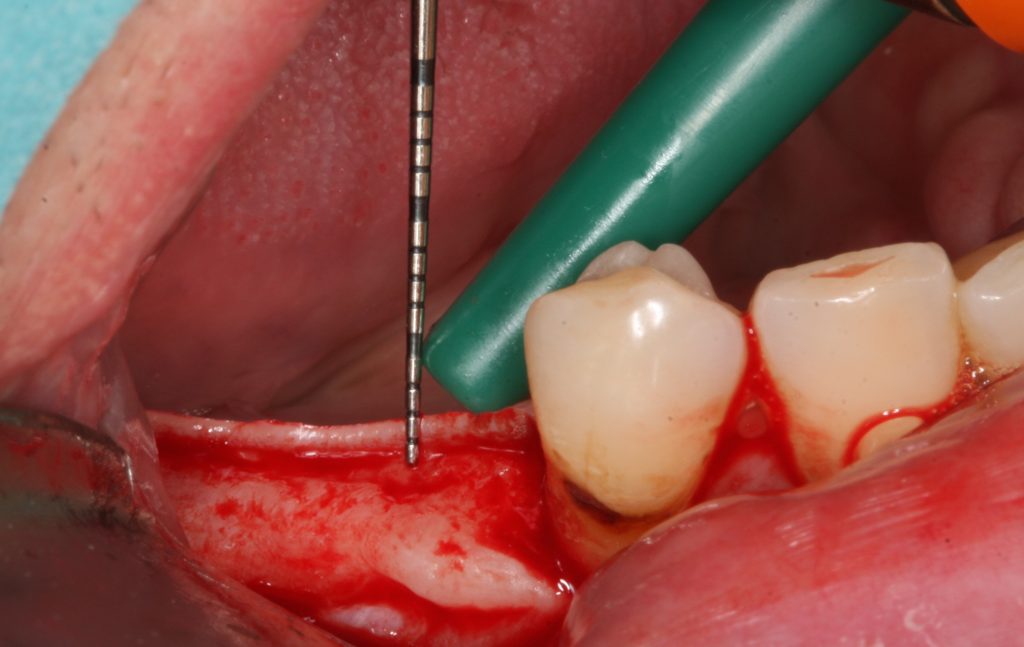

The first thought, which enters the mind, just places implant deeper subcrestally (Fig 5). Firstly, there must be enough place for the alveolar nerve that the implant could be positioned subcrestally in a safe manner.

It is advised that the implant would stop at least 1 mm over the nerve. Subcrestal placement is suggested to cause controlled bone remodeling, but not a bone loss. It is interesting to note, that not all implants can be placed subcrestally. In addition, implant-abutment connection stability becomes very important, if located subcrestally.

Screenshot at ..

Placement of implants subcrestally leads to bone remodeling, implant neck remaining unexposed

Another option might be recontouring of the bone during basic implant bed preparation, especially if narrow ridge is present.

Careful reduction and smoothening of the narrow ridge not only will provide a flat bone surface and a sufficiently wide area of bone for implant positioning, but would increase soft tissue thickness as well.